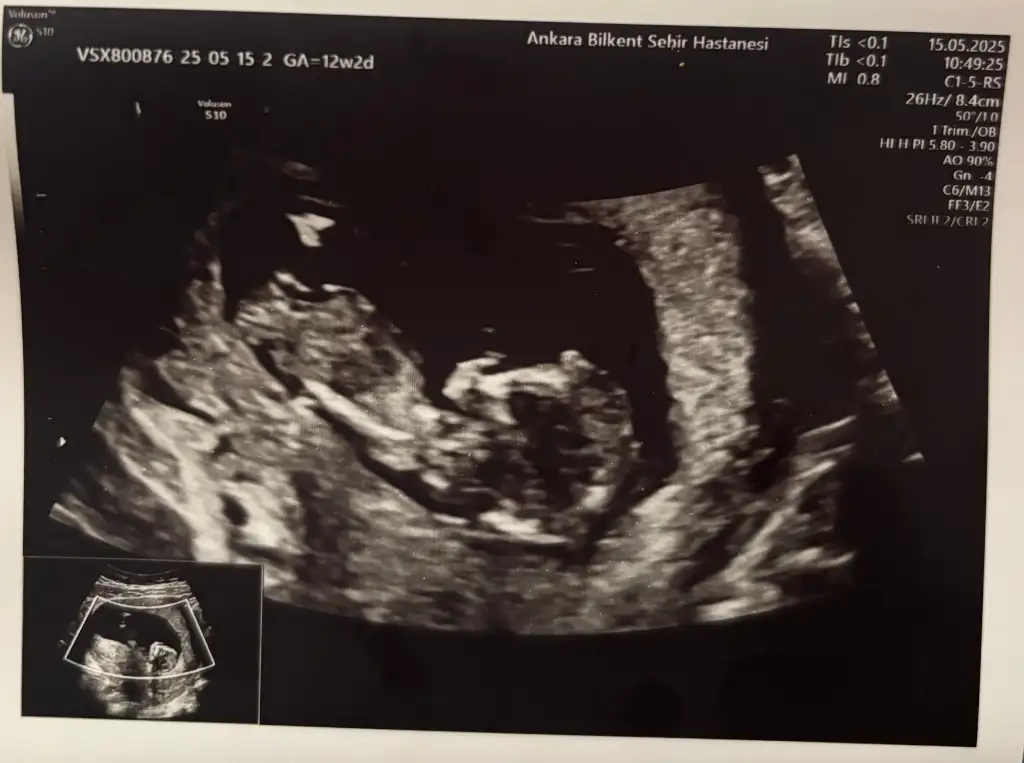

Banada bakarmısınızKarındansa erkek vajinalse kız ramziye gore

Kız benceLütfen banada bakın 8 haftalık

Merhaba karından bakıldı yorumlarsanız çok mutlu olurum 8 haftalıkKarındansa erkek vajinalse kız ramziye gore

Kız bakmayın bana ben kendimce tahmin yapıyorum anladığımdan değil yani daha kendi bebeme bile yorum yapamıyorumMerhaba karından bakıldı yorumlarsanız çok mutlu olurum 8 haftalık Eki Görüntüle 3589013

Plasenta göre erkek diyorumMerhaba karından bakıldı yorumlarsanız çok mutlu olurum 8 haftalık Eki Görüntüle 3589013

Ay sağlıkla inşallah diyorumPlasenta göre erkek diyorum